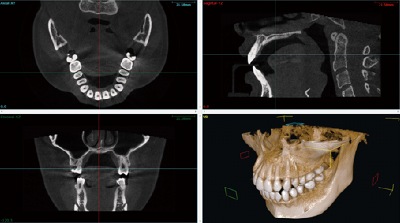

医院概要:ホワイト歯科は2007年9月より私、森 康仙が診療を行っております。明るい笑顔と、わかりやすい説明で患者さんをお迎えする病院です。皆様が安心して治療が受けられるよう、院内は感染予防にも努め、機械や器具の消毒、医療スタッフの手洗いには「ハイクロソフト酸性水システム」を利用した殺菌水を使用。 当医院ではオルソパントモ、デンタルX線のデジタル化が完了いたしました。デジタル式はフィルム式と比べて被爆量が少ないので女性の方やお子様など安心して撮影することが出来ます。 また、フィルムや現像液、洗浄液、定着液を使用しませんので地球エコ、環境にも優しいという利点があります。デジタル撮影は現像処理がないため撮影後すぐにモニターで見られるので患者さんの待ち時間の減少がかなり期待できます。